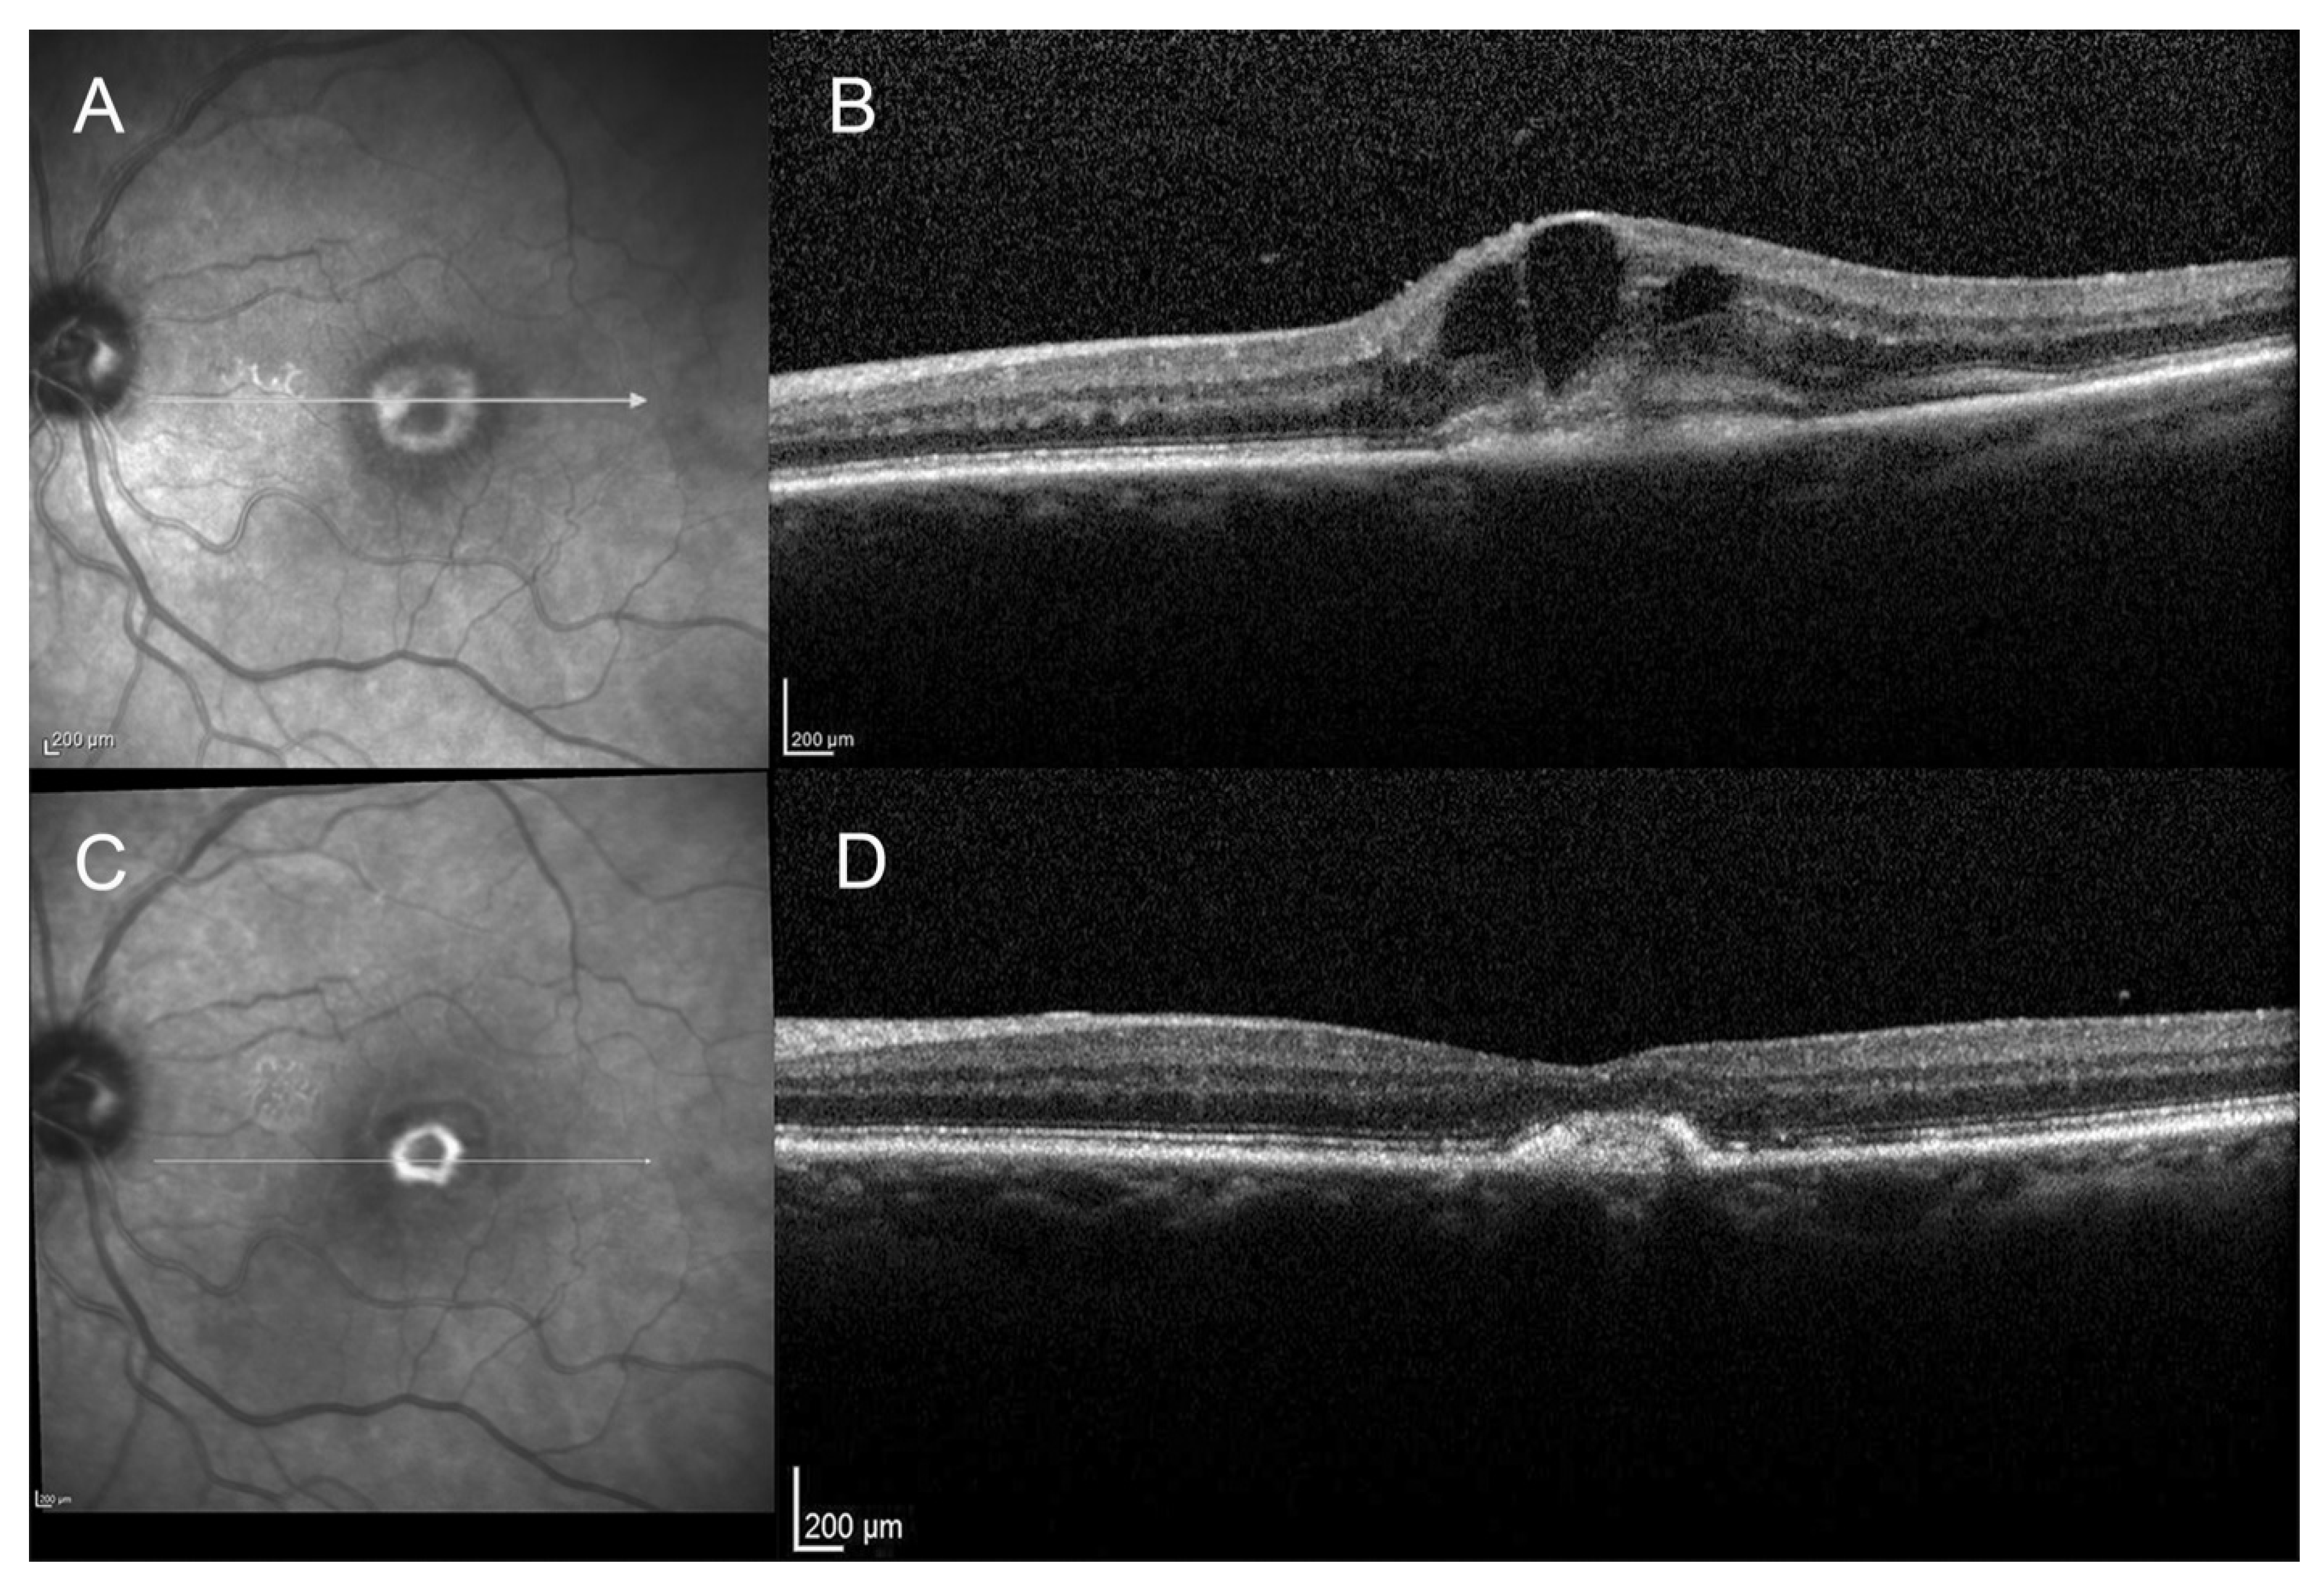

Progression from Type 2 Macular Neovascularization to Fibrovascular Pigment Epithelial Detachment

3. Results

3.3. Anatomical Outcome

4. Discussion